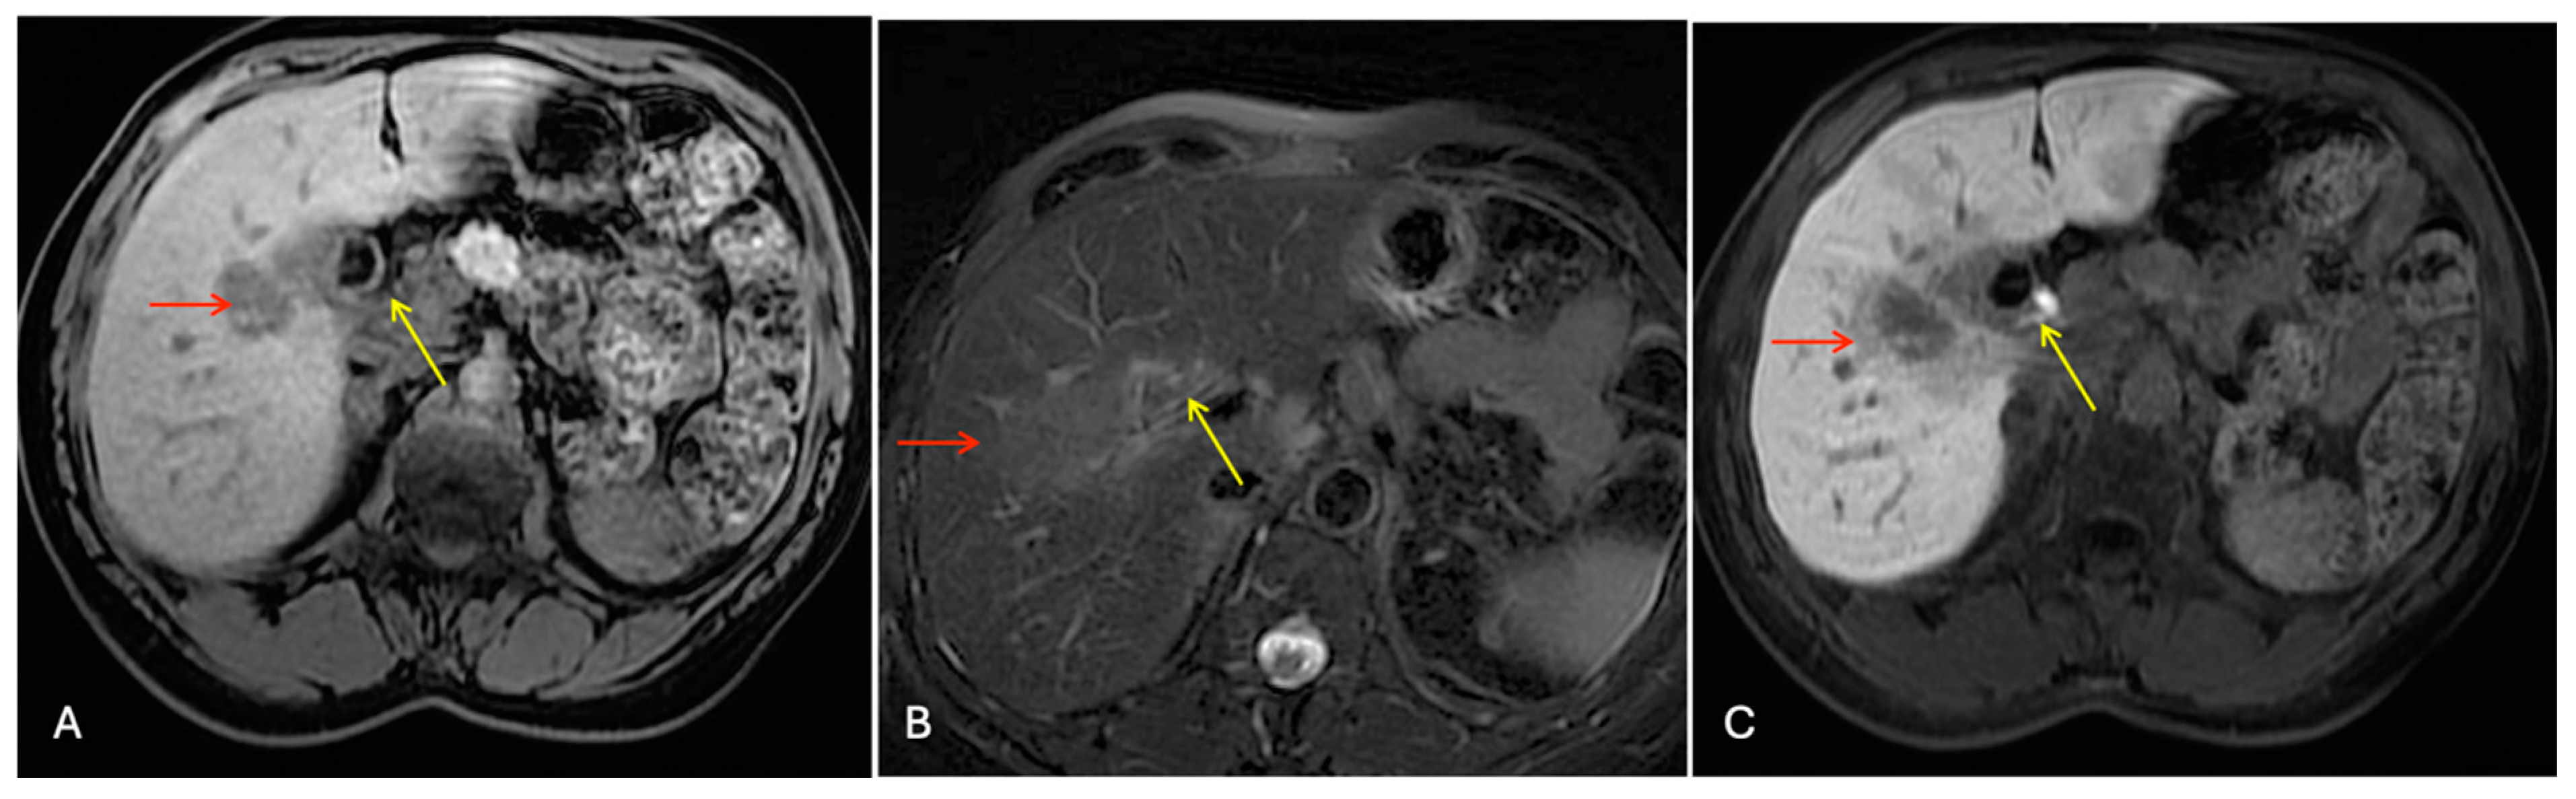

3.2.1. Case 1